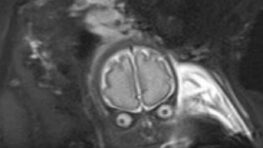

Une britannique enceinte de son deuxième bébé était obligée de faire une IRM du cerveau à l’enfant dans son ventre…